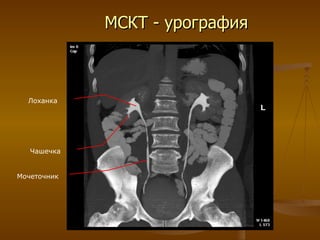

МСКТ - урография Чашечка Лоханка Мочеточник

МСКТ - урографияЧашечка Лоханка Мочеточник